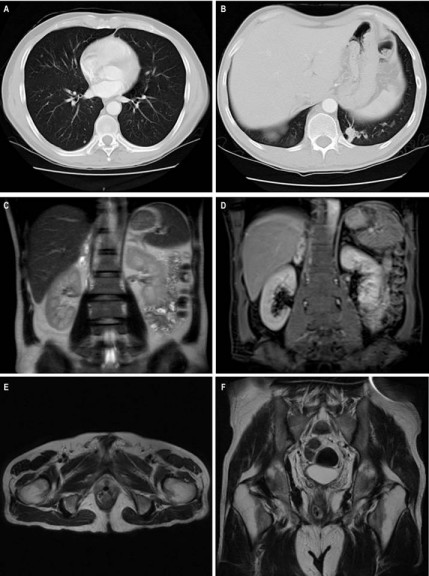

Le realizaron una rectosigmoidoscopia, en donde se evidenció una lesión neoplásica en la ampolla rectal a 5 cm del reborde anal, cuya biopsia reportó un carcinoma escamocelular moderadamente diferenciado. Una resonancia magnética de pelvis evidenció, a nivel del canal anal, un engrosamiento neoplásico con zona de ulceración focal anterior en contacto con la uretra membranosa y ápex de la próstata. La resonancia magnética de abdomen reportó lesiones metastásicas en glándula suprarrenal derecha, adenopatías paraaórticas izquierdas e infrarrenales, retrocavas, en eje celíaco y retrocrurales derechas. La tomografía de tórax reportó múltiples adenopatías tumorales en región axilar derecha, supraclaviculares, prevasculares, paraesofágicas, retrocrurales derechas y paraaórticas izquierdas. Adicionalmente mostró una lesión nodular cavitada en la base del pulmón izquierdo y múltiples nódulos subcentimétricos con densidad de tejidos blandos de distribución aleatoria, sospechosos de malignidad (Figura 1).